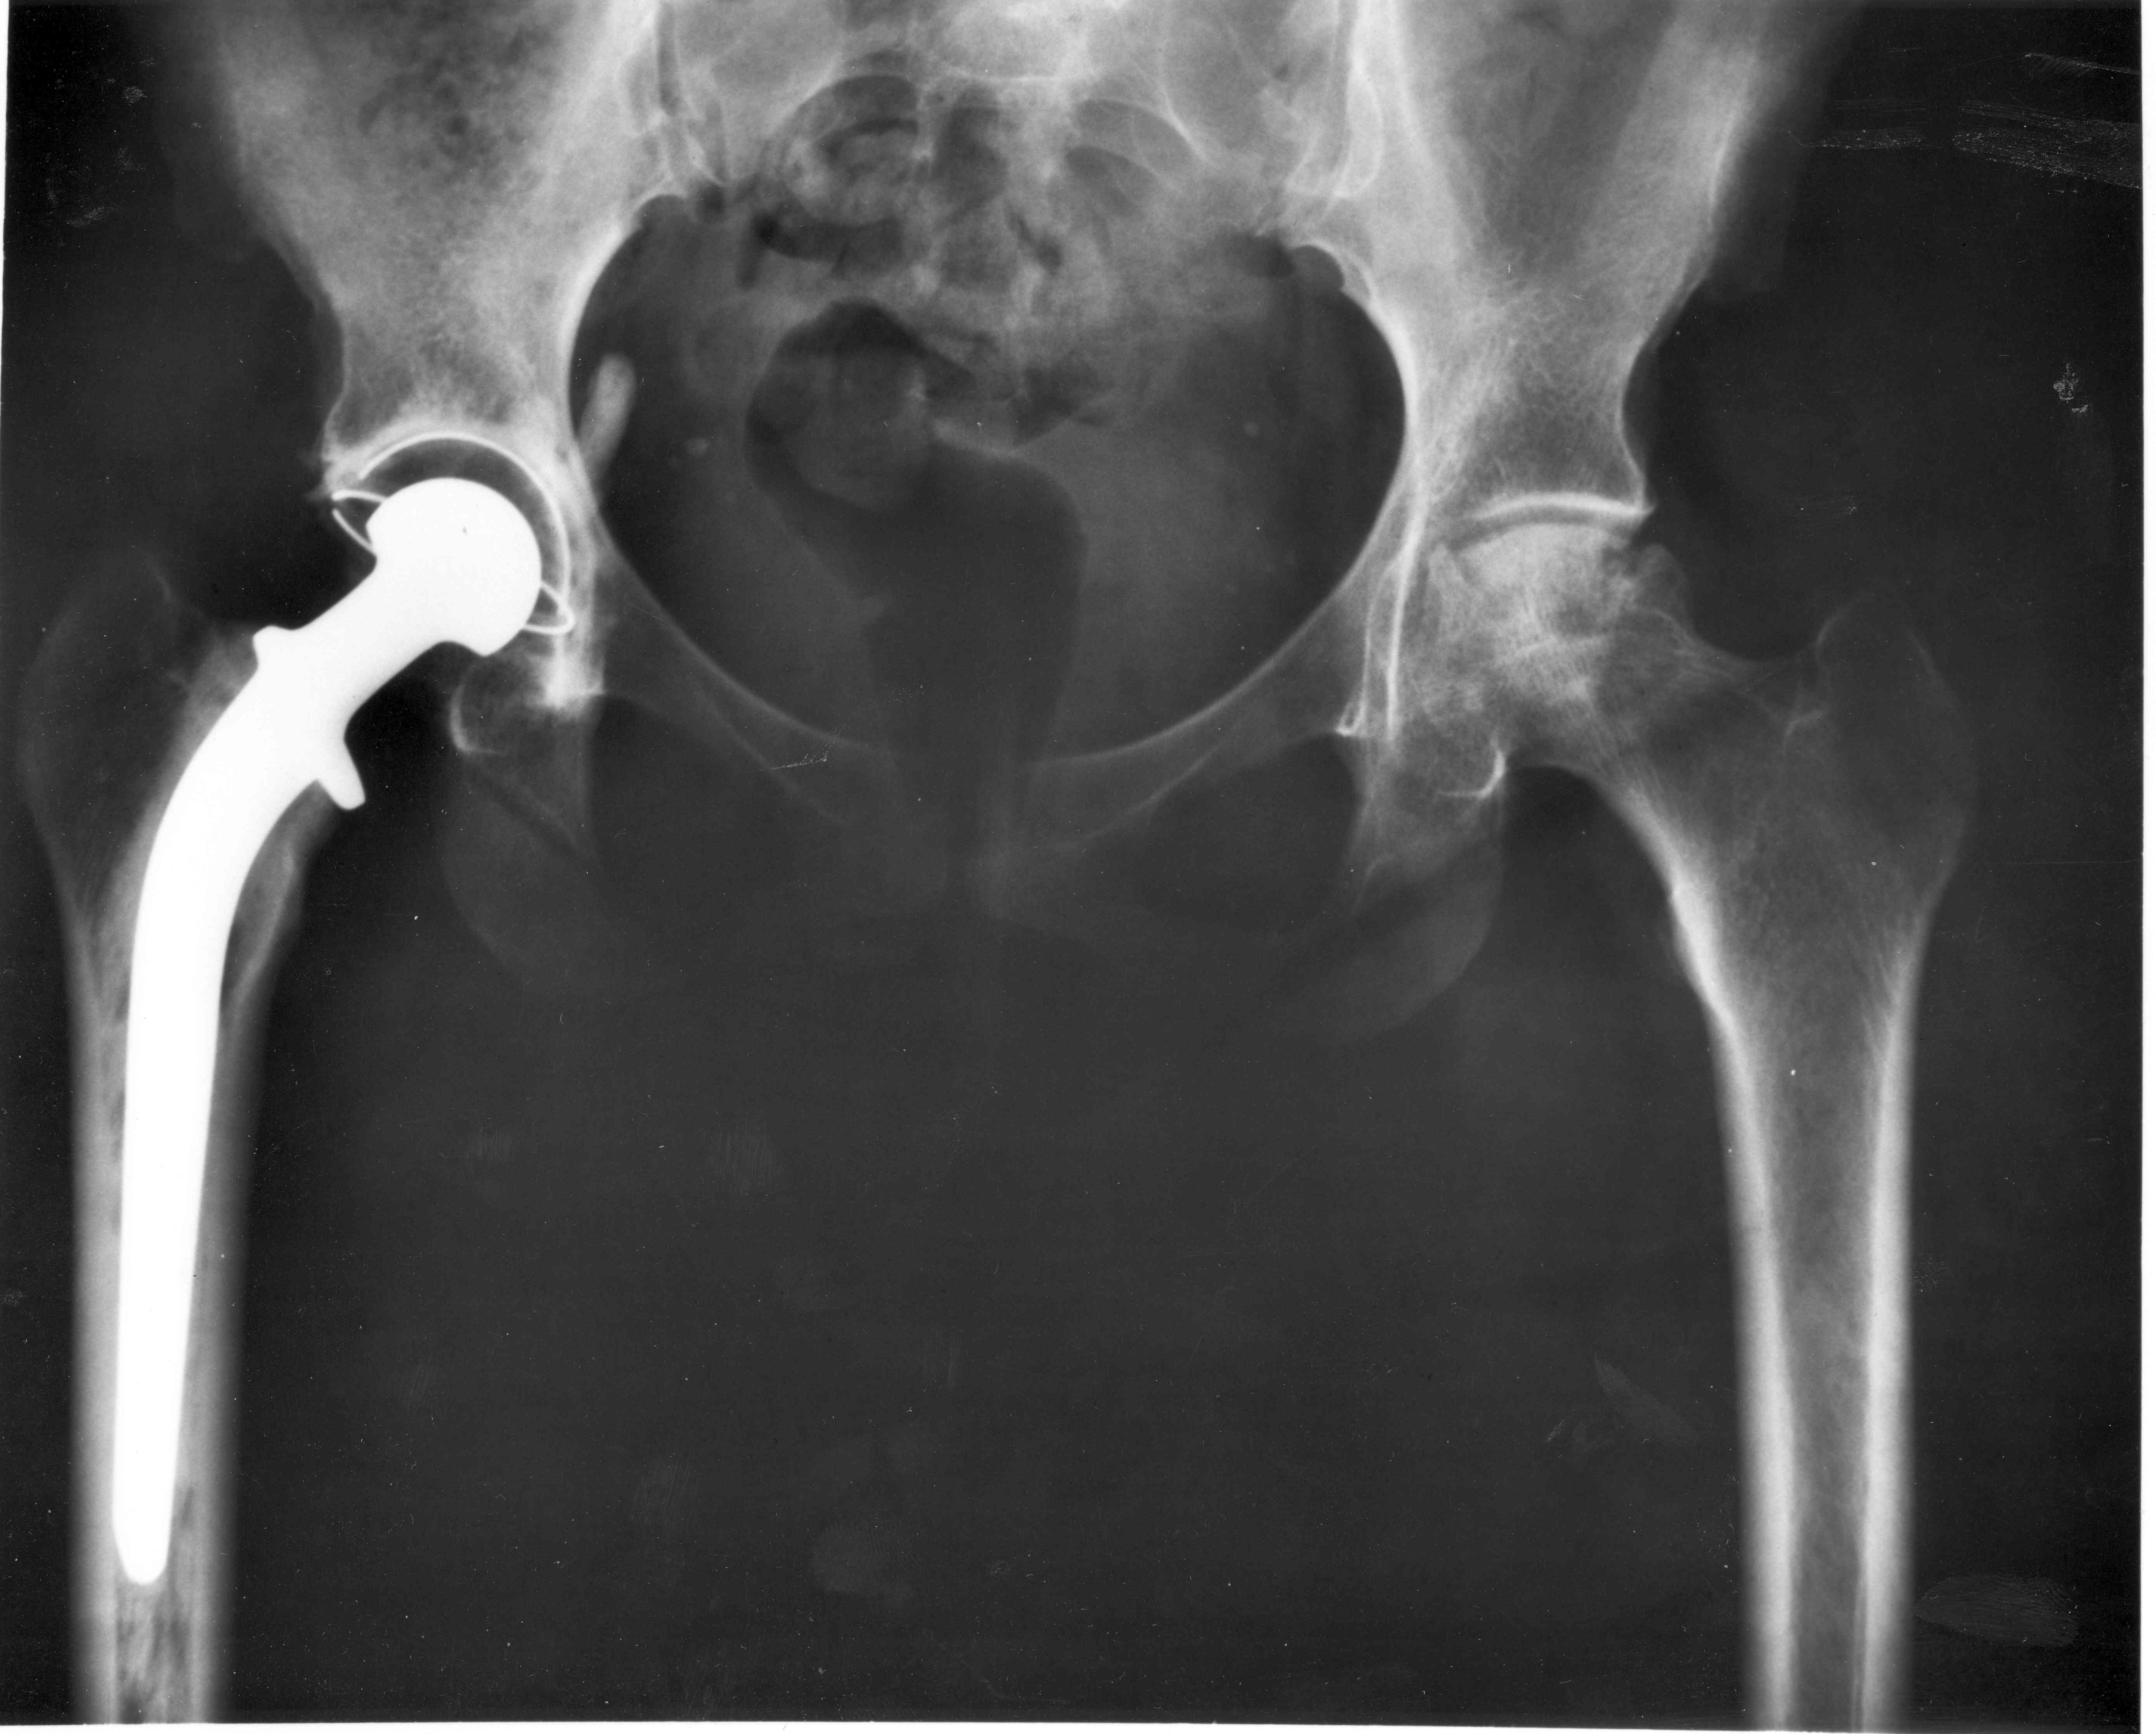

| Описание | An A-P X-ray of a pelvis showing a total hip joint replacement. The right hip joint (on the left in the photograph) has been replaced. A metal prostheses is cemented in the top of the right femur and the head of the femur has been replaced by the rounded head of the prosthesis. A white plastic cup is cemented into the acetabulum to complete the two surfaces of the artificial "ball and socket" joint.

Although not the case here, hip prostheses can also be made of a ceramic material which rarely wears out during the patient's lifetime. During the operation, a bonding cement is used to fix the metal prostheses into the shaft of the femur and the plastic cup to the acetabulum (socket in the hip bone). One of the leading reasons for hip replacement is osteoarthritis of the hip joint in which virtually all of the cartilage around the top of the femur bone deteriorates due to wear over time, leaving a grinding bone-on-bone situation with the bone surfaces becoming roughened leading to pain and stiffness. Narrowing of joint space (the space between the acetabulum and the head of the femur) is also a feature of osteoarthritis. There may be other changes which are not entirely clear on this A-P X-ray, which probably should be reported together with lateral X-rays of the hips, or with modern computerised imaging techniques. Keywords: total hip replacement, prosthesis, osteoarthritis, X-ray. |